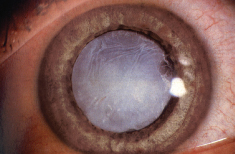

原发性青光眼泛指并非由其他疾病所致的青光眼。而继发性青光眼是由其他眼疾或身体疾病引致,例如过熟的白内障丶葡萄膜炎丶眼球肿瘤丶糖尿眼丶或长期使用类固醇眼药水。要治疗继发性青光眼,必须先处理引致青光眼的疾病。 -